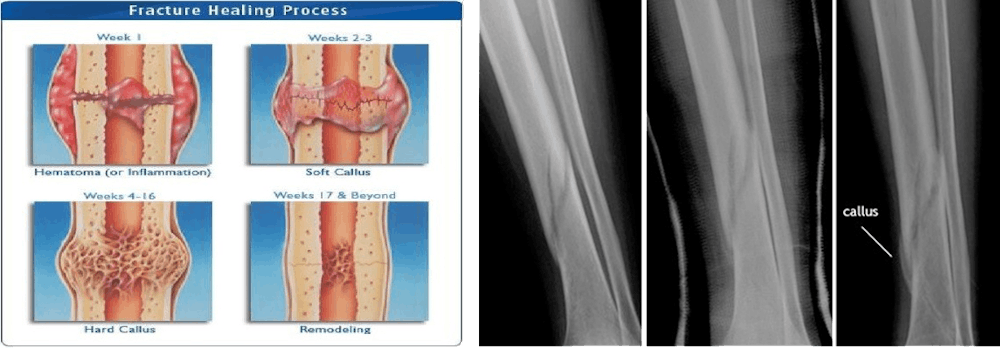

As soon as one of your bones breaks, your body springs into action to fix the injury. The time it takes for a bone to heal depends on a lot of things, such as the person’s age and location of the break.

Step 1: Blood Clot Formation and Cleanup

Within a couple of hours, a blood clot forms around the break. Inside the blood clot, special cells called phagocytes begin cleaning bone fragments.

Step 2: Soft Callus Formation

Next, another special group of cells called chondroblasts creates a soft callus made mostly of collagen around the fracture. This stage can last anywhere from 4 days to 3 weeks.

Step 3: Hard Callus Formation

A hard callus forms next as osteoblast cells create new bone, adding minerals to make it hard. This stage typically begins two weeks after the break and ends somewhere between the sixth and 12th week.

Step 4: Bone Remodeling

Lastly, the bone is remodeled. Special cells called osteoclasts break down extra bone around the fracture until it’s completely healed and returned to its original shape. Bone remodeling is a very slow process which can take anywhere from 3 to 9 years to complete!